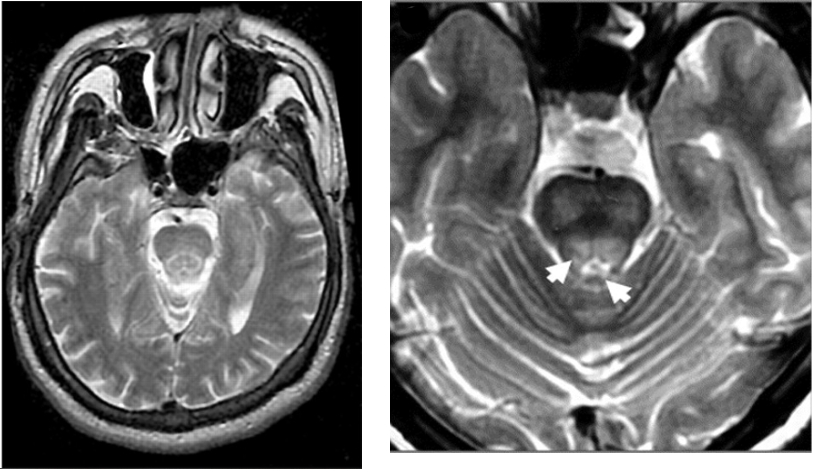

Typical MRI changes include symmetrical hyperintense or mixed intensity T2- weighted and FLAIR signal change in the striatum, especially the putamen, and also the thalamus, midbrain and pons.

The cerebellum, corticospinal tracts, and subcortical areas (atrophy in 70% of cases) are also affected.

Classical radiological signs include:

Face of the giant panda sign (referring to the combination of high signal intensity in the tegmentum except for the red nucleus (eyes) with preservation of signal intensity of the lateral portion of the pars reticulata of the substantia nigra (ears) and hypointensity of the superior colliculus (mouth).

This may be associated with the “cub” sign in which similar appearances are seen within the pontine tegmentum.